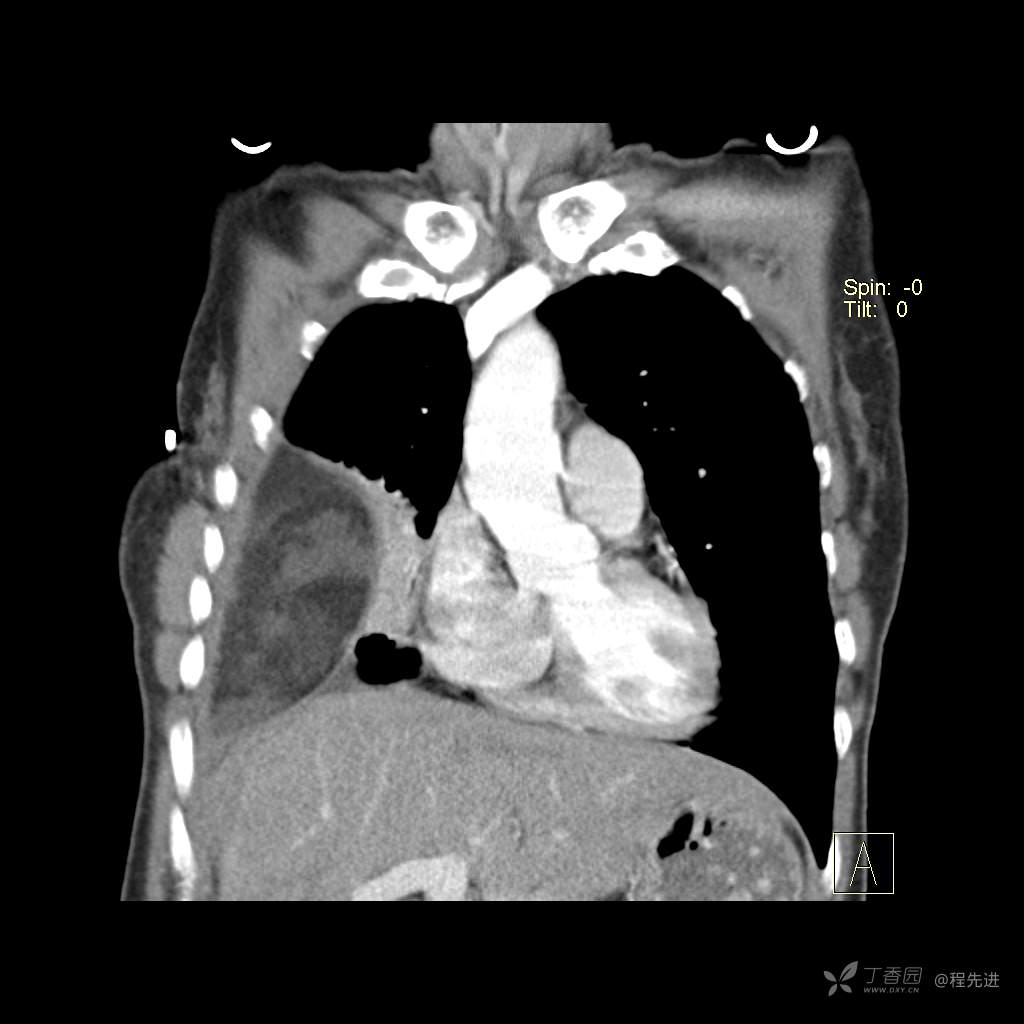

患者性别:女

患者年龄:51岁

简要病史:胸闷半年

肺淋巴管肌瘤病 (7)

乳糜胸 (8)